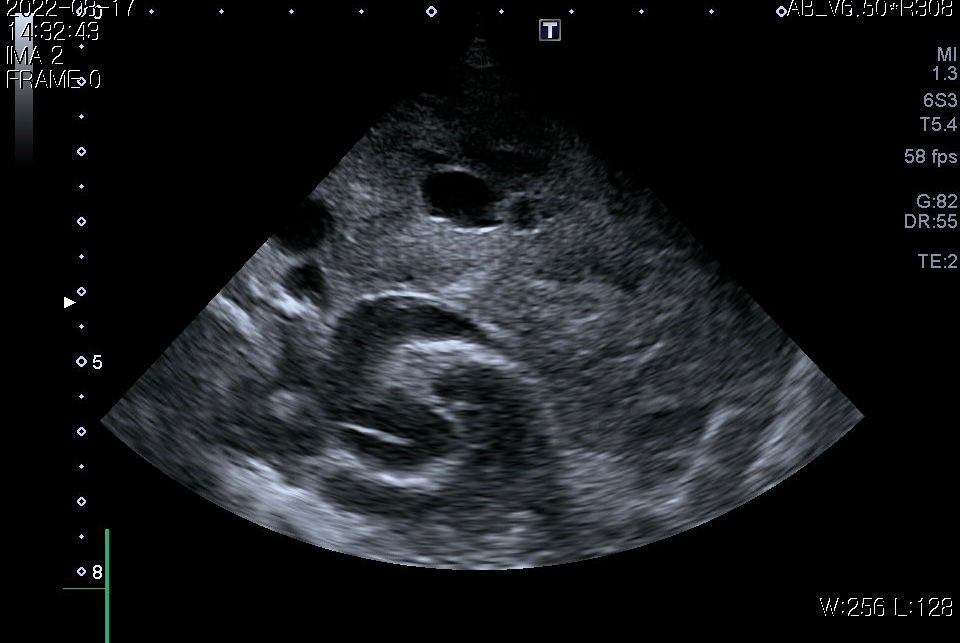

첨부해주신 사진만을 기초로 볼때 폐종양인 경우 좌측 폐전엽부의 종양이, 폐종양이 아닌 경우 종격동내의 종양 특히 흉선종양의 가능성이 높아 보입니다.

이 두가지 종양의 가능성이 사실 가장 높은 상태에서 CT 촬영을 해보아야 하는 이유는

또한 흉선종인 경우 이정도 크기로 증가하는 경우에는 대부분 adenocarcinoma인 경우가 많고 그런 양상인 경우 혈관이나 미주신경 침습등의 가능성이 높아 수술불가 판정이 나올 수 있습니다.

이런 경우에는 인터페론 치료와 면역계 치료, 항암, 방사선 요법, 중제적 시술을 통한 크기 줄이기등 비 수술적 요법이 적용되어야 합니다.

앞으로의 처치 방향을 결정하기 위해서라도 CT 촬영을 통해 수술 가능종양인지, 수술을 하지 않더라도 다른 중재적 시술이나 내과적 치료의 플랜을 짜야 하는 상황이라고 보시면됩니다.